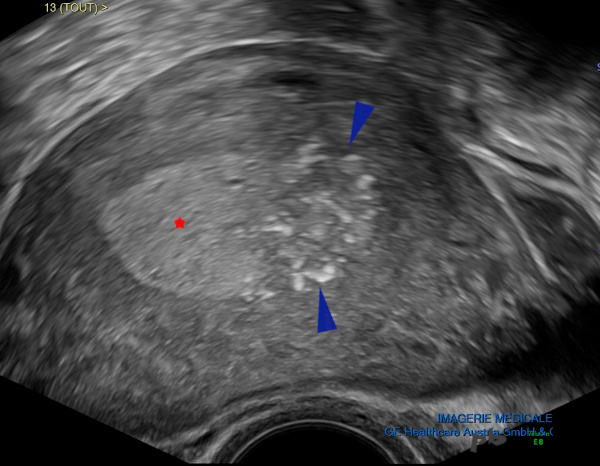

- Polypes : images 7 à 13 (Voir aussi chapitre « Exploration d’un endomètre épais » images 5 à 14)

- Polyps: images 7–13 (See also the chapter “Exploring a Thickened Endometrium,” images 5–14)